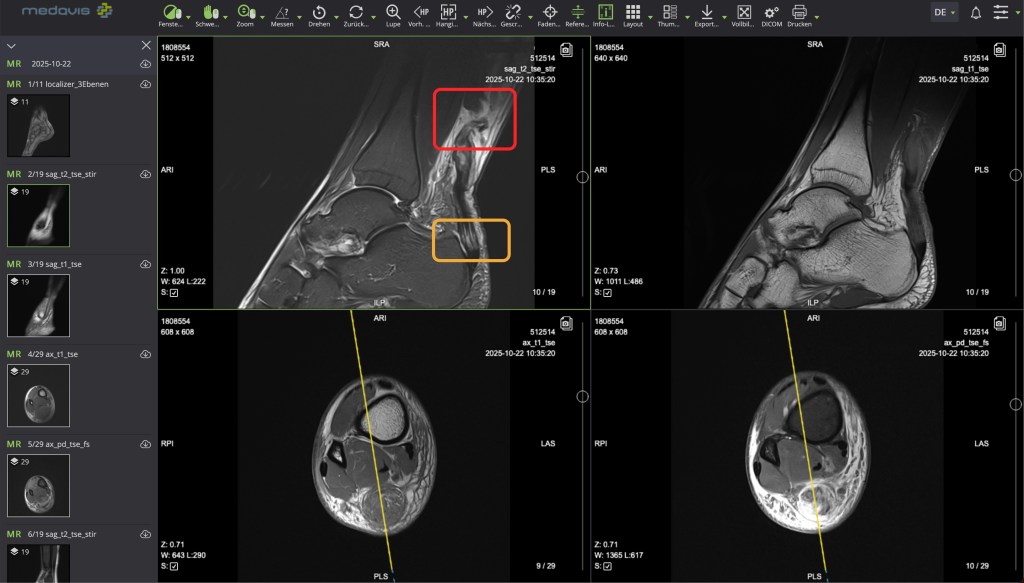

Later at home I went through the MRI pics on my laptop: below, red is the tear, orange is a somewhat damaged section … unlikely to have happened at the same time, I was told; possibly tendinopathy from the past … which led to some speculation that the tear might have occurred due to previous damage. Initially, though, either way: torn is torn!